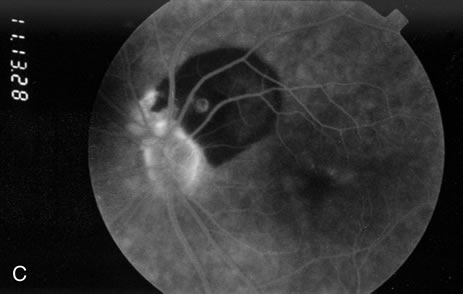

Retinal arterial macroaneurysms often produce retinal edema, circinate hard exudates, and hemorrhage (Fig. 3) into multiple layers of the retina: beneath the retinal pigment epithelium, beneath the retina, within the retina, beneath the internal limiting membrane, between the retina and the posterior hyaloid, and within the vitreous cavity. When the macroaneurysm is obscured by overlying blood, its diagnosis can be challenging.

Fig. 3. A. Color fundus photograph of a macroaneurysm along the inferotemporal arcade with surrounding intraretinal and subretinal hemorrhage. There is retinal edema, hard exudates, and thin subretinal hemorrhage extending into the macula. B. Midphase fluorescein angiography reveals hemorrhage that extends just into the foveal avascular zone, threatening foveal vision. C. Late-phase angiogram reveals staining of the macroaneurysm. D. Color fundus photograph of the same macroaneurysm 6 weeks after laser photocoagulation, demonstrating resolution of the edema and hemorrhage.

Because of rapid blood flow through retinal arterial macroaneurysms, they typically fill quickly in the early phase of the fluorescein angiogram. In the mid- and late-phases of the angiogram, the macroaneurysm tends to leak to varying degrees, depending on its perfusion and endothelial integrity (Fig. 3C). If there is subretinal fluid surrounding the aneurysm, there may be pooling of dye into the subretinal space. In some cases, a characteristic Z-shaped kink may be identified at the site of the aneurysm.

Perfusion abnormalities caused by the macroaneurysm cause changes in the surrounding retinal vasculature as well, and this is best visualized on fluorescein angiography (Fig. 3B). Ischemia from stagnation of blood flow results in capillary telangiectasis, microaneurysm formation, and capillary nonperfusion.

Some or all of these angiographic features may be obscured by blood or lipid exudation from the aneurysm. If blood collects in front of the retinal vessels (vitreous hemorrhage, preretinal hemorrhage, subinternal limiting membrane hemorrhage, or intraretinal hemorrhage), then blockage of hyperfluorescence may be partial or complete. Subretinal blood blocks hyperfluorescence from the choroid but not the retinal circulation, resulting in dramatically distinct retinal vessels against a dark background (Fig. 3B,C). Lipid exudation and retinal edema may cause partial blockage of hyperfluorescence.